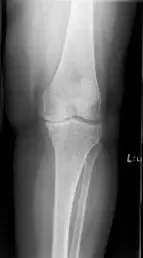

Su examen físico reveló sensibilidad articular con crepitación. Había sensibilidad en la línea articular medial y en la faceta de la rótula medial. Los estudios de imagen revelaron osteoartritis bicompartmental de la rodilla con obliteración del espacio articular del compartimento medial y del compartimento patelofemoral.

Radiografía preoperatoria de la rodilla izquierda que muestra la visión AP y lateral